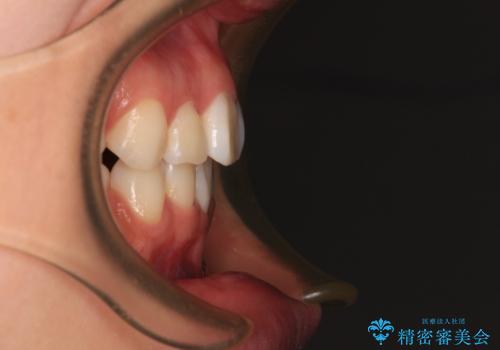

- 歯のデコボコや八重歯、クロスバイトを気にして来院された患者様です。

上下左右第一小臼歯4本を抜歯し、ワイヤー装置にて歯列を整え、さらには少しでも口元を引っ込めるよう矯正治療を行うこととしました。